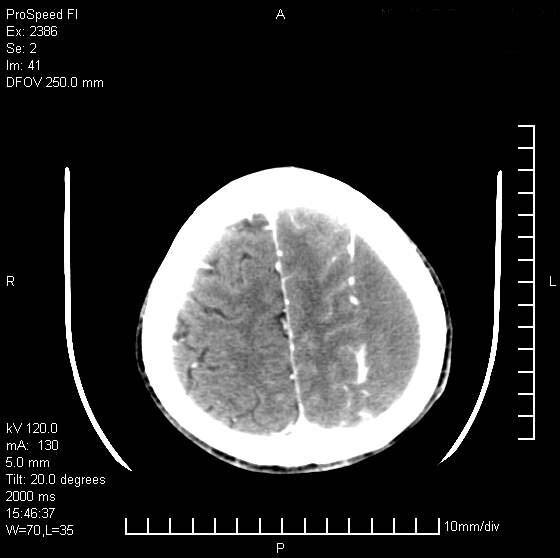

以下是引用天南地北在2007-9-19 18:43:00的发言:[br]典型慢性硬膜外血肿[br][br][本贴已被 天南地北 于 2007-9-19 18:44:11 修改过]

以下是引用曼一拍在2007-9-20 11:06:00的发言:[br]支持慢性硬膜下血肿.[br]慢性硬膜下积液:血肿有包膜,ct值稍高于脑脊液,增强可有染色。不典型者血肿可多呈梭形.是硬脑膜与蛛网膜之间的潜在腔隙内的血肿。[br]鉴别:[br]1\\硬膜外血肿:是颅脑外伤后脑膜或板障内血管破裂,血液在颅骨与硬膜之间积聚所致.通常是脑膜动脉破裂,也可因静脉窦破裂或颅骨的板障静脉出血,发生于外伤的着力部,常与颅骨骨折并存。脑膜动脉出血则急,若是板障静脉出血在则可有慢性。[br]2\\硬膜下积液:(硬膜下水瘤)[br]是由于蛛网膜破裂,脑脊液经蛛网膜破口进入硬膜下腔不能回流。或水肿阻塞而形成。[br]ct表现:颅骨内板下方新月形低密度区近似脑脊液密度;占位效应清,周围无脑水肿。[br]